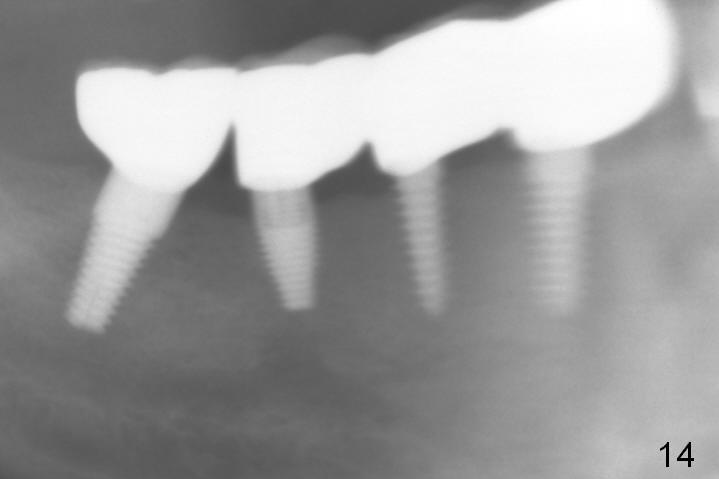

The lower right bridge (from canine (Fig.2: 3) to 1st molar (Fig.1: 6)) fails while a 77-year-old man is undergoing chemotherapy for urinary bladder cancer. The abutments of the bridge are extracted without plan for implants (Fig.4). Four months later, the patient returns for implants (Fig.3), but the ridge is narrow (Fig.5). While 2 of 3x14 mm 1-piece implant are placed at the canine and 1st bicuspid sites, 2 piece ones at the 2nd bicuspid and 1st molar sites (Fig.6: 3.5x11 mm, 5x14 mm). Soft (Fig.7-10) and hard (Fig.11) tissues heal 1 week (Fig.7) and 4 months (Fig.8-11). There is minimal bone resorption 1 year 7 months post cementation (Fig.12,13, non-splinting). It appears that narrow diameter implants are a valid solution to narrow ridge at the sites of the lower canine and premolar. As long as there are enough implants for function, the crowns are not necessary to be splinted. Surprisingly, the patient starts flossing after implant restoration. Retrospectively an immediate provisional bridge should have been fabricated.

There appears to be no bone loss 2 years 5 months post cementation (Fig.14). Gingival bands form around the implants at #27-29 three years 1 month post cementation (Fig.15 *).